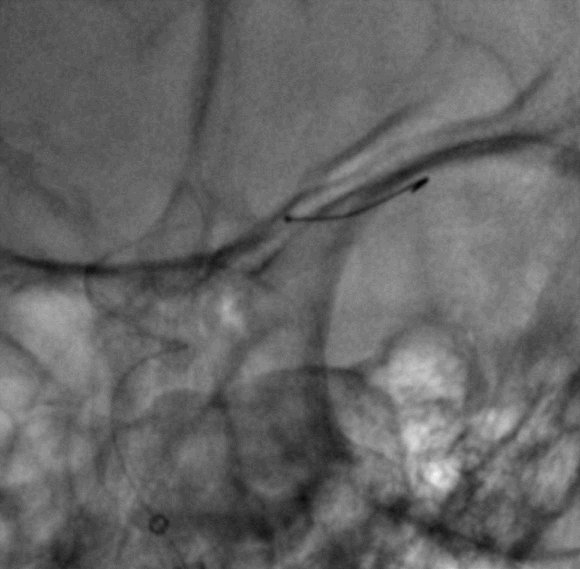

Cat5完全释放支架后,拉推送杆后支架近端打开,后将Cat5跟进血流导向装置内尝试“按摩”,支架整体贴壁不够理想。

Cat5通过后海绵窦段狭窄即较前改善

Cat5提供稳定通路,引入3.5mm×10mmHiryu球囊扩张由远端及近端扩张狭窄段及支架贴壁欠佳处

造影示狭窄及贴壁较前进一步改善

导丝成袢,继续“按摩”改善贴壁

“按摩”后再次造影,C2段狭窄仍较明显且贴壁欠佳

再次引入球囊扩张近端

扩张后再次复查造影示支架打开及贴壁较前明显改善

标准正侧位造影未见远端血管栓塞

稀释造影提示支架贴壁可,狭窄改善